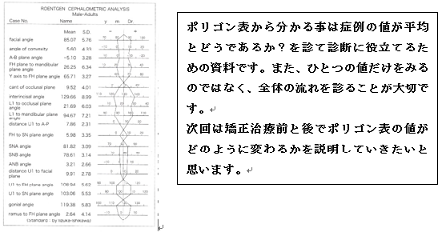

実際の治療でポリゴン表はどのように変化するか?診てみましょう。

第5版 歯科矯正学 図18-21 治療前後の側面頭部エックス線規格写真分析

13項目のうち8項目の数値が悪くなっています。

矯正治療を始めて間もない先生は治療前より治療後がポリゴン表の値は必ず良くなると思っているようですが、そうならない事も多々あります。

それは、矯正学の最終目標が個性正常咬合の確立であって、ポリゴン表の値をそろえる事では無いからです。